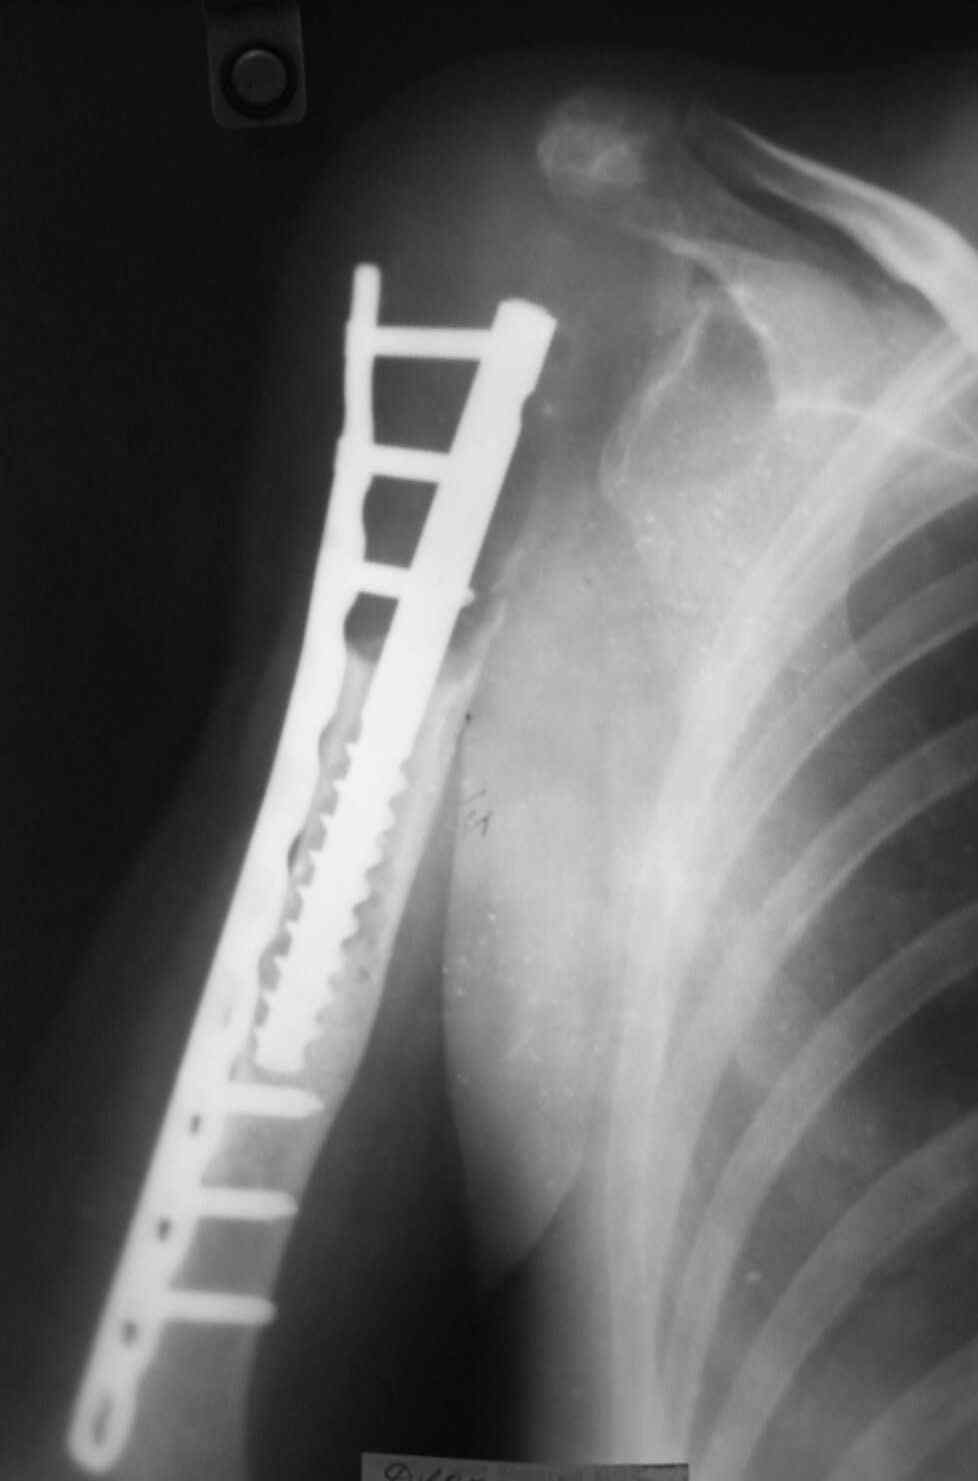

Больная 34 года операрована 14 лет назад по поводу литической формы ОБК головки плечвой кости

14 лет назад больной имлапнтирован протез плечевой кости выполненый по методике Воронцова на штифте-штопоре Сиваша,за 2 года до имлапнатации в онкологическом учереждении больной выполнена резекция проксимальоной части плечевой кости по поводу ОБК, ксенотрансплантации головки, и последующем его удалением на фоне гнойного процесса. У больной имелся втянутый обширный рубец и болтающееся плечо, афункциональная верхняя конечность, выраженный косметический дефект.П/опрационный период без осложнений, сохранялась выраженная контрактура в плечевом суставе, но стаилизация плеча и косметический эффект больную устраивал,даллее контакт с больной был утерян ( поменяла место жителсьтва. Через 14 лет полноценной жизни сельской жешщины ,больная нашла нас с клиникой выраженной нестабильности протеза. Категорически отказалась от замены протеза.

Выполнена операция- малоинвазивно проведена LCP пластина в образованный канал над головкой протеза, фиксирована к протезу и дистально к плечевой кости, на зоной резорбции трепонирована кость, удалена соединительно-тканная оболочка, полость заполнена chronOS. П/о период без осложнений, клиника нестабильность купирована.Прошло 2 года по телефону сообщила, что у нее все хорошо, продолжает жить счастливой жизнью сельской труженицы